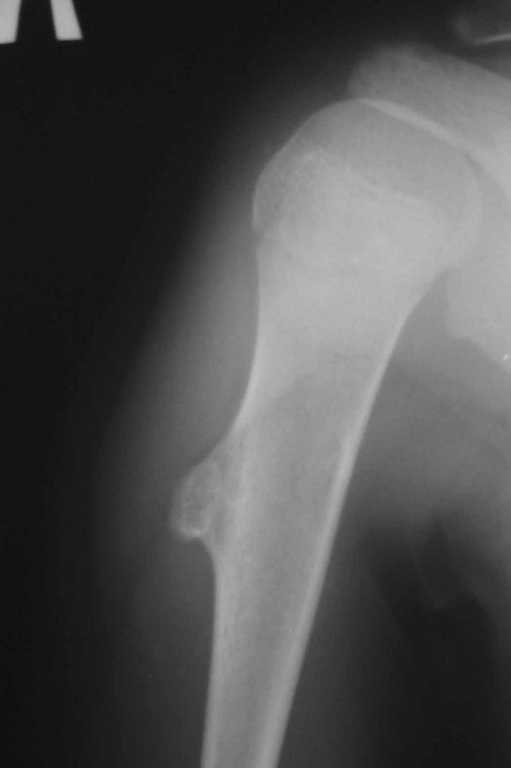

Энхондрома (?)

У 12-летнего мальчика образовалась припухлость на верхней трети плеча.

Рентгенобслежование выявило такую картину. Нельзя исключить энхондрому диафиза плечевой кости. Какую тактику лечения выбрать: экскохлеация или сегментарная резекция? Какие ортопедические центры, имеющие опыт лечения данной патологии, можно рекомендовать родителям мальчика для консультации и возможного, качественного, лечения? Спасибо.